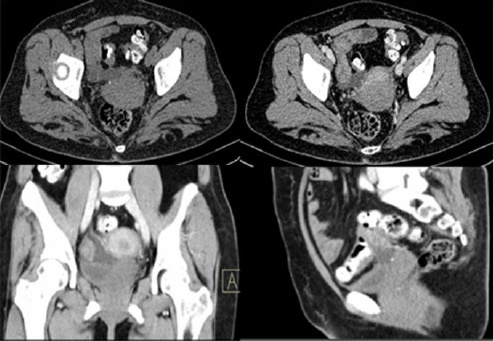

Paralelamente cuenta con tomografía computarizada por estudio de sangrado uterino anormal evidenciando lesión hipodensa en fondo de saco vesicouterino sugestiva de probable endometriosis (Figura 3).